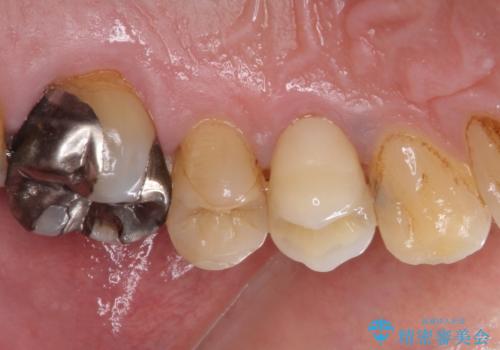

割れてしまった小臼歯 インプラントによる補綴治療

- 他院で抜歯が必要と診断され、再度診断を希望して来院された患者様です。

顕微鏡下で診察を行ったところ、歯根が垂直に破折していたため、抜糸してインプラントによる補綴治療を行うこととしました。

より審美的で、より機能的に優れた治療をご希望とのことであったので、ジルコニアカスタムアバットメントを用いたインプラント治療を行うこととしました。